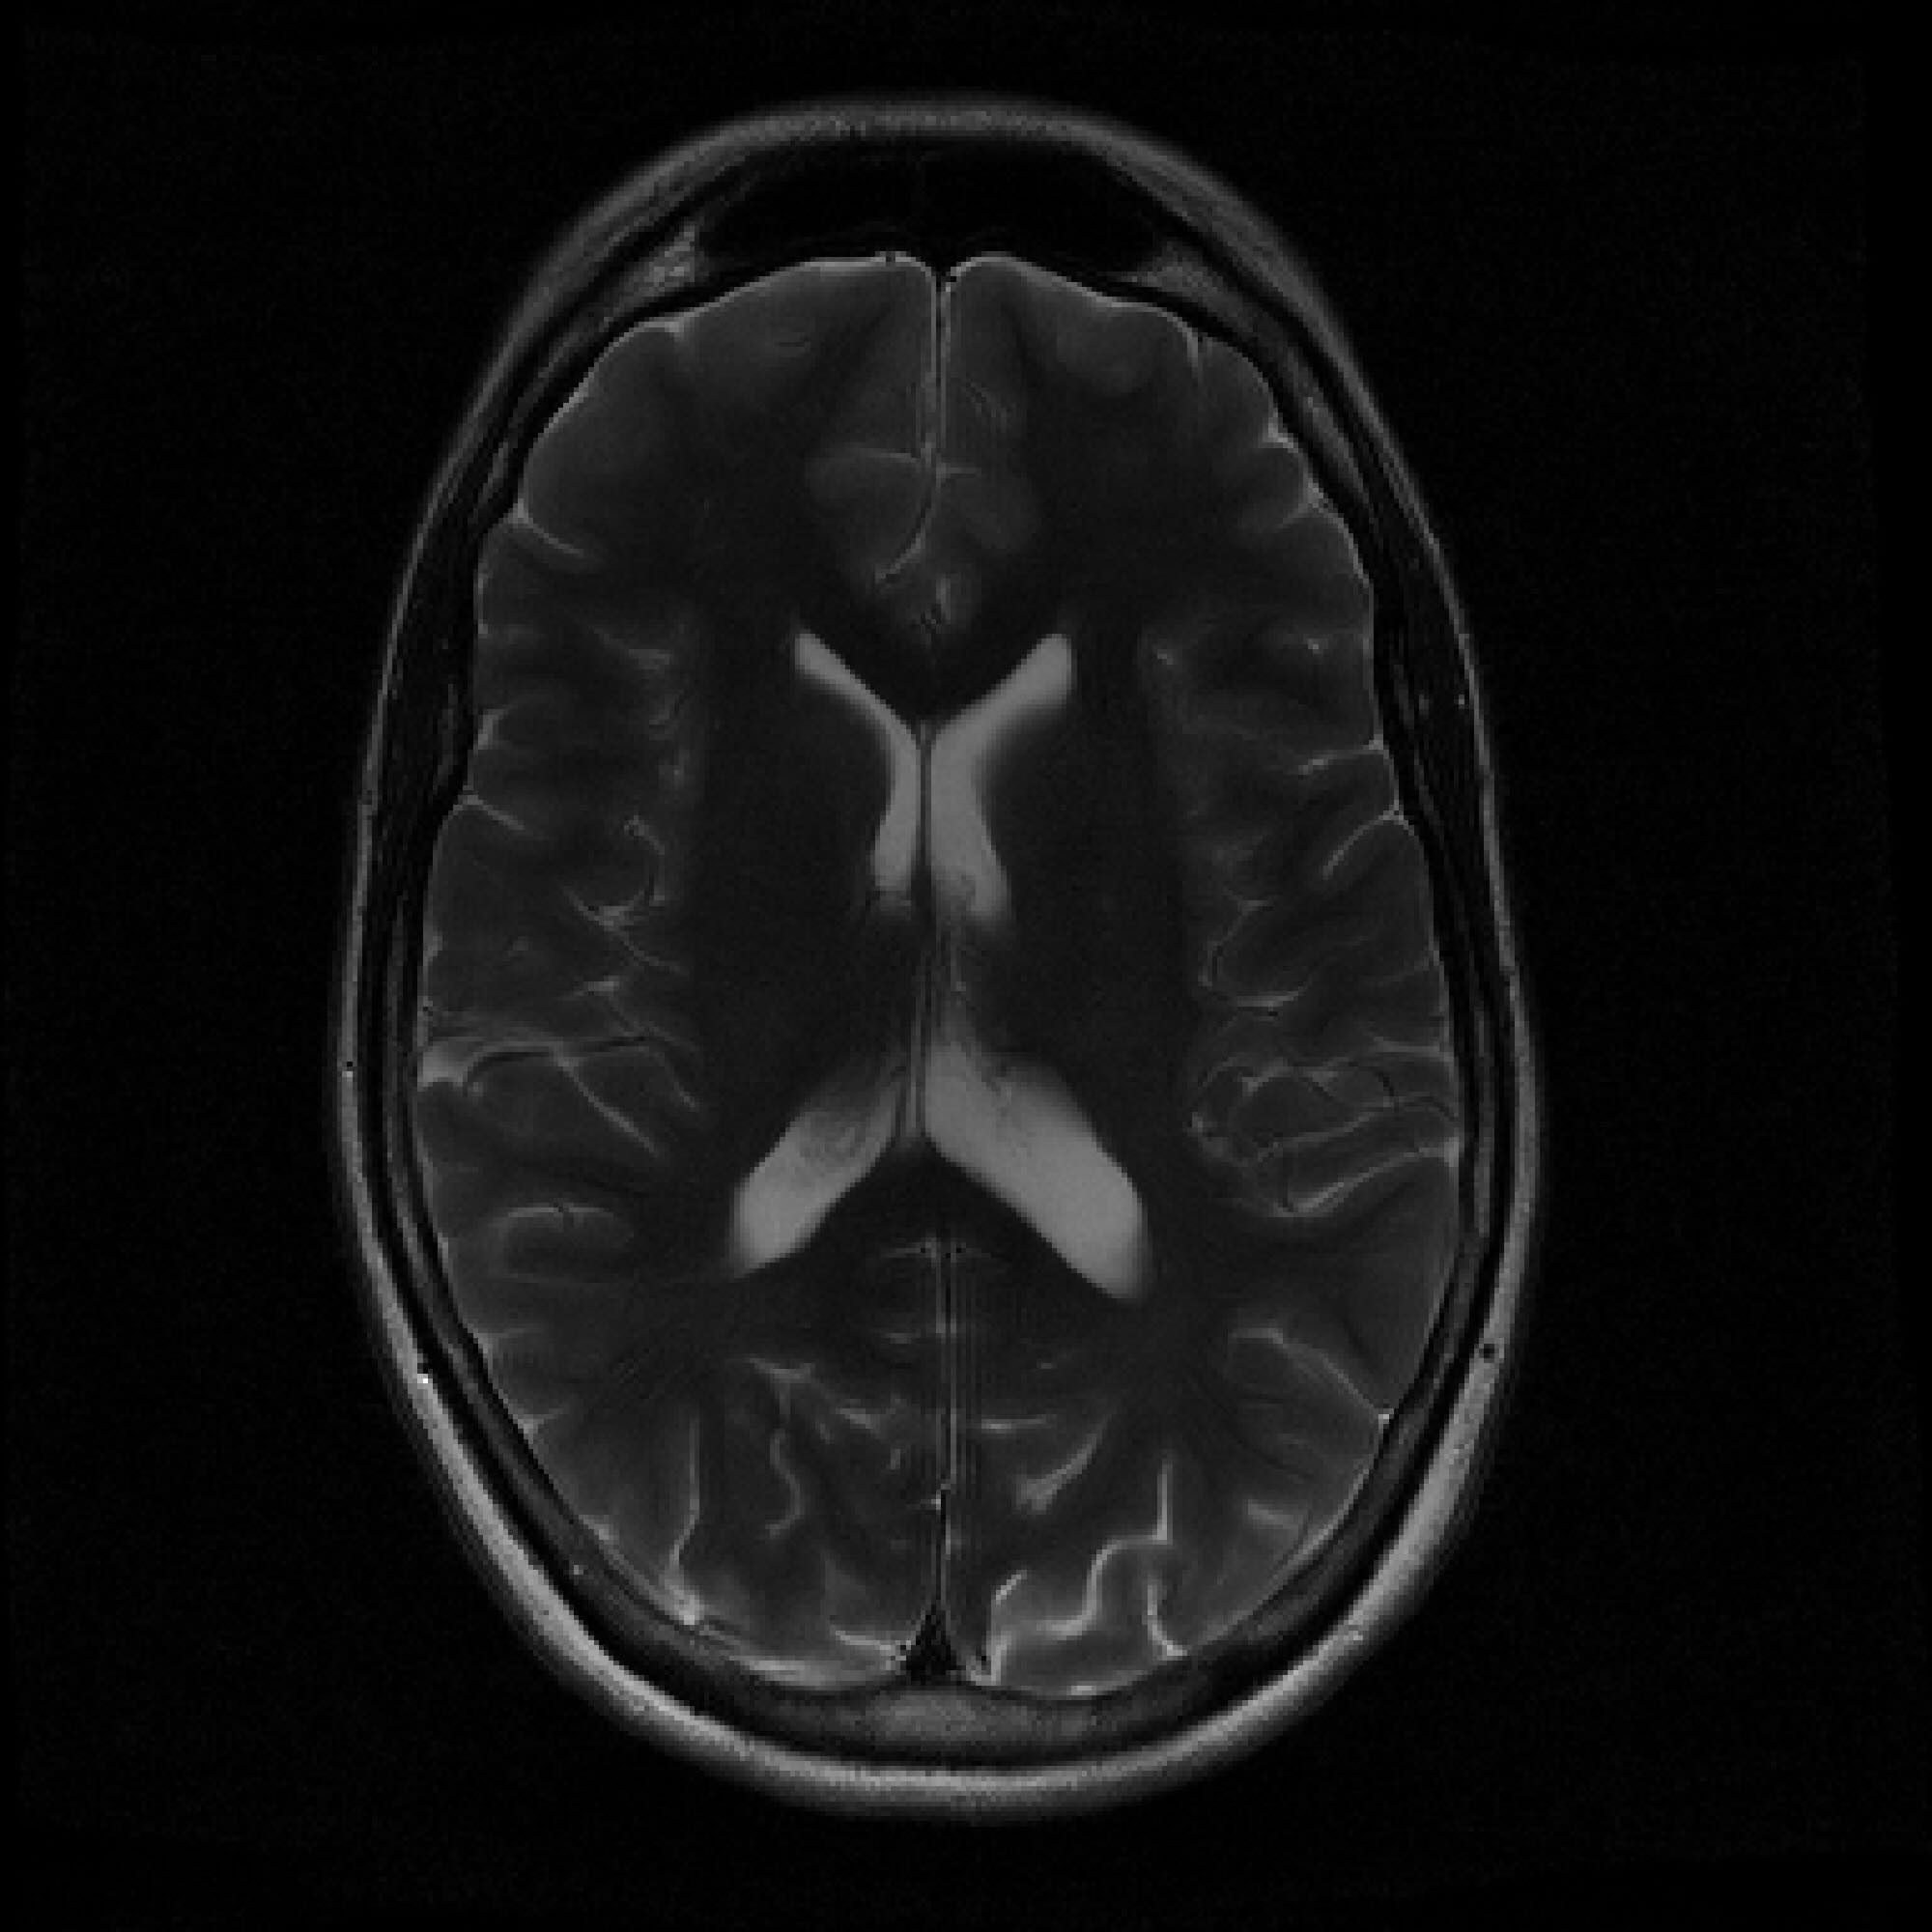

Refer to caption

Figure 2: Example MRI magnitude reconstructions with S=25S=25 training slices at acceleration (undersampling) factor R=7R=7. PaDIS-MRI reconstructions are sharper and more faithful to the fully-sampled ground truth. Insets are shown to the right to highlight detail.

Figure 2 provides a visual comparison of the reconstruction quality of each method on example slices. In reconstructions from the S=25,R=7S=25,R=7 models, FastMRI-EDM exhibits slightly more blurring and loss of fine structural details, particularly in regions with complex anatomical features. PaDIS-MRI, in contrast, preserves sharper boundaries and finer details. This enhanced data efficiency can be attributed to the patch-based prior’s ability to learn localized structural motifs more effectively from limited examples. Figure 6 in the Appendix shows similar reconstructions at S=200,R=7S=200,R=7 where FastMRI-EDM more closely approaches the performance of PaDIS-MRI but still struggles with highly detailed anatomy.